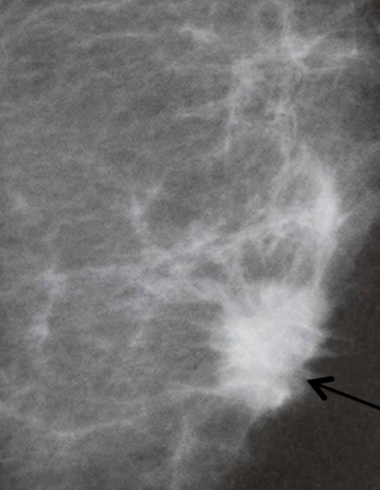

A woman presents with a hard breast lump with irregular borders. She has had surgery on her breast in the past. Mammogram is performed

Fat necrosis

What is this breast pathology that may mimic breast cancer on mammogram?